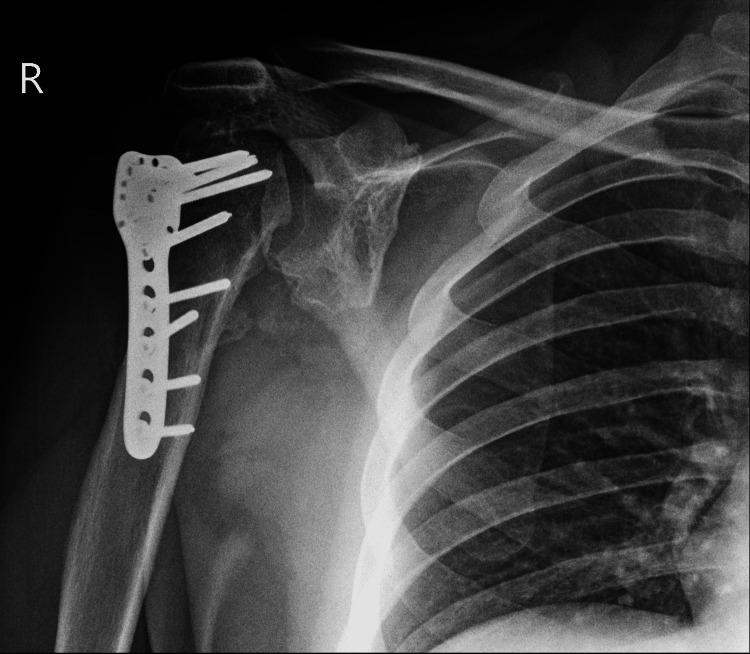

Bilateral shoulder dislocations are a rare occurrence and can be categorized as either symmetric (both humeral heads dislocate in the same direction) or asymmetric (wherein the humeral heads dislocate in different directions). Shoulder dislocations may be overlooked if they are the result of systemic injury; if diagnosed >21 days after occurring, they are considered chronic dislocations. We describe the case of a 31-year-old male who presented with an eight-week history of bilateral shoulder pain. His onset of pain coincided with a seizure secondary to Chikungunya encephalitis. Clinical and radiological examination demonstrated bilateral symmetric anterior shoulder dislocation with associated greater tuberosity fractures and extensive callus formation bilaterally. Open surgical management was performed first on the left shoulder via the deltopectoral approach. The callus was removed, the greater tuberosity fragment lifted off, reattached to the original position, and held in place with sutures and proximal humeral locking plates. The right shoulder was reduced six weeks after the left shoulder due to patient preference; the reduction utilized the same approach as with the left shoulder. Post-operatively the patient was immobilized, and physiotherapy commenced. He achieved a satisfactory range of motion four months post-operation. Physicians should be cognizant that shoulder pain after a convulsive seizure may signify shoulder dislocation. Thorough clinical and radiological examinations are warranted in such an instance. There exists no consensus on the treatment of chronic shoulder dislocations, but it is recommended that closed reduction only be attempted up to six weeks post-dislocation due to the high risk of iatrogenic fractures and neurovascular damage beyond this time.

双侧肩关节脱位较为罕见,可分为对称型(两个肱骨头向同一方向脱位)或不对称型(肱骨头向不同方向脱位)。如果双侧肩关节脱位是由全身损伤导致的,可能会被忽视;如果在脱位发生21天以后才被诊断出来,则被视为慢性脱位。我们报告一例31岁男性患者,其双侧肩部疼痛长达8周。他的疼痛发作与基孔肯雅热病毒性脑炎继发的癫痫发作同时出现。临床和影像学检查显示双侧肩关节对称前脱位,伴有大结节骨折及双侧广泛骨痂形成。首先通过胸大肌三角肌入路对左肩进行切开手术治疗。清除骨痂,将大结节骨块掀起,重新复位并固定到原始位置,用缝线和肱骨近端锁定钢板固定。由于患者的选择,右肩在左肩手术后6周进行复位;复位采用与左肩相同的方法。术后患者进行制动,并开始物理治疗。术后4个月,患者的活动范围恢复到令人满意的程度。医生应认识到惊厥性癫痫发作后的肩部疼痛可能意味着肩关节脱位。在这种情况下,有必要进行全面的临床和影像学检查。对于慢性肩关节脱位的治疗目前尚无共识,但由于脱位超过6周后进行手法复位会有较高的医源性骨折和神经血管损伤风险,因此建议仅在脱位后6周内尝试进行闭合复位。